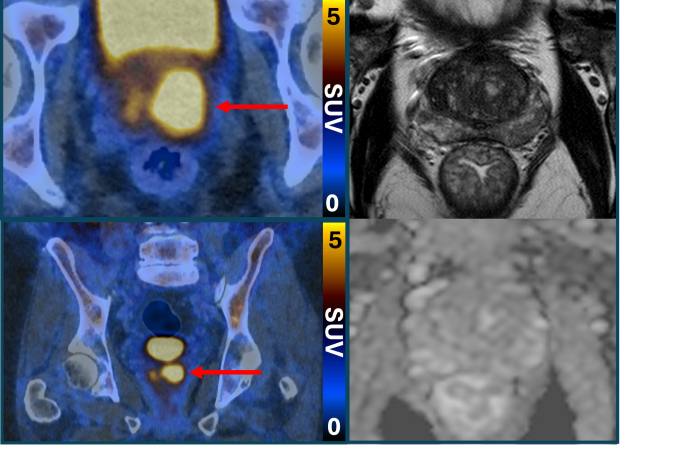

O exame PET/CT (tomografia por emissão de Pósitrons/tomografia computadorizada) com PSMA identifica células agressivas presentes na próstata, que são potencialmente prejudiciais e podem precisar de tratamento. Isso é possível graças a uma molécula que se liga a essas estruturas e as faz brilhar, aparecendo como pontos luminosos na imagem. O estudo afirma que isso também pode ajudar a reduzir o risco de sobrediagnóstico.

O ensaio descobriu que a tomografia por emissão de pósitrons (PET/CT) com PSMA podia identificar pessoas que não tinham câncer ou cujo tumor era de tão baixo risco e com crescimento tão lento que provavelmente nunca causaria danos. Esses pacientes não precisaram de biópsia. A nova abordagem reduziu pela metade o número de pessoas submetidas ao exame invasivo, sem deixar de detectar nenhum câncer maligno.

A abordagem também beneficiou os pacientes que ainda precisavam de biópsia. Os resultados da tomografia garantiram que o procedimento fosse direcionado às áreas suspeitas identificadas no exame de imagem, a fim de minimizar complicações e aumentar a precisão.